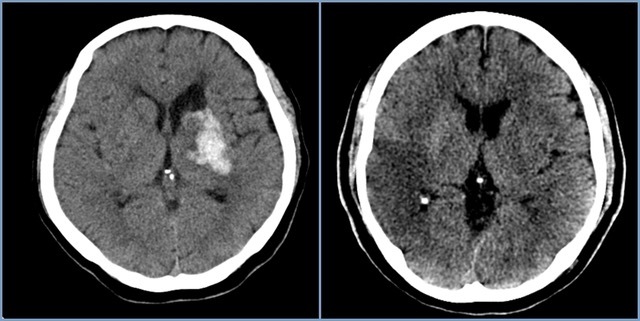

뇌경색이란 무엇인가요?

뇌경색은 뇌의 특정 부위에 혈액이 공급되지 않아 발생하는 문제입니다. 주로 혈관이 막히거나 좁아져 혈액이 제대로 흐르지 않을 때 발생하죠. 전 세계적으로 많은 사람들이 이 질환으로 고통받고 있으며, 특히 노인층에서 빈번하게 발생합니다. 뇌경색을 예방하고 조기에 발견하는 것이 중요한 이유는 이 질환이 뇌에 큰 손상을 줄 수 있기 때문입니다.